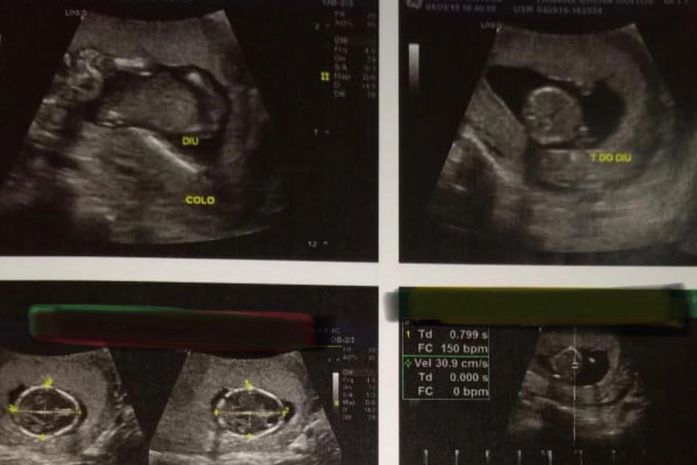

Por meio de uma nota técnica, o Conselho Regional de Enfermagem de Alagoas (Coren-AL) afirma que o procedimento de implantação do Dispositivo Intrauterino, o DIU realizado pelo enfermeiro na cidade de Penedo esteve dentro das normas estabelecidas pelo Ministério da Saúde. A jovem sofreu um aborto após o procedimento.

O Conselho afirma ainda que, antes da inserção, foi realizado um teste rápido de gravidez, além da anamnese, onde não foi identificada nenhum indício da gravidez da paciente. Todas as medidas foram tomadas durante a consulta com assinatura do termo de consentimento livre e esclarecido pela usuária, onde foram expostos todos os benefícios e riscos do procedimento, entre eles os riscos da inserção no caso de gravidez em evolução.